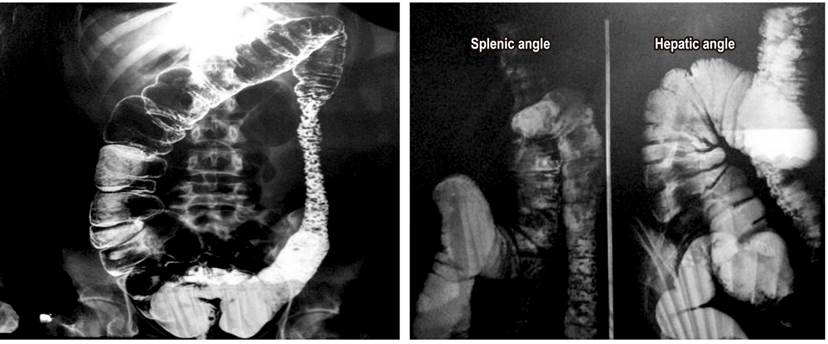

A complete blood count and blood chemistry were normal. In addition, barium enema abdominal radiography found alterations of the colonic frame with accumulation of secretion (Figure 1). In the rectosigmoidoscopy, more than 100 polyps of sizes ranging from 3 mm to 5 cm were observed from the distal ascending colon to the rectum. Some were pediculate and others were sessile, tubular and villous in appearance (Figures 2 and 3).

Figure 1 Abdominal barium enema radiography in standing anteroposterior projection shows evidence of colonic wall thickening, irregular dilations of the colonic frame, increased amounts of heterogeneous secretions in the ascending colon, hepatic angle, descending colon and sigmoid colon with multiple polypoid images and correlative signs with collar ulcers.